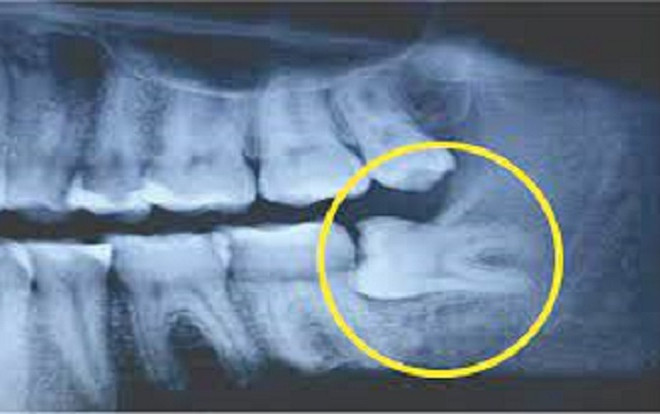

Sau khi có kết quả  chụp X-Quang, bác sĩ chẩn đoán do 1 răng khôn của Lin mọc ngầm và lệch nên mới dẫn đến tình trạng đau nhức. 3 chiếc răng khôn khác cũng bị ảnh hưởng.

Bác sĩ đã chỉ định Lin nhổ răng khôn bằng phương pháp gây mê. Trong đó, cô có thể chọn gây tê cục bộ hoặc toàn thân trong khi phẫu thuật. Sau khi thảo luận với mẹ, cô Lin quyết định nhổ bỏ cả 4 chiếc răng khôn bằng cách gây mê toàn thân.